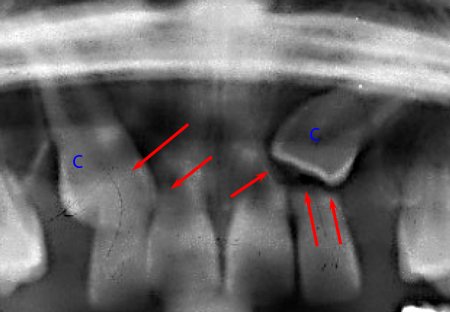

Rétention des Prémolaires

La 2e prémolaire inférieure est la plus concernée. Signes cliniques :

- Persistance des molaires lactéales sans mobilité

- Perte prématurée des molaires lactéales avec migration mésiale des 1ères molaires

- Absence ou réduction de l’espace d’éruption

- Résorption des racines des dents adjacentes

- Apparition de diastèmes antérieurs

- Version distale de la dent adjacente mésiale par pression coronaire de la dent incluse sur la racine

- Perturbation globale des rapports intra et inter-arcades